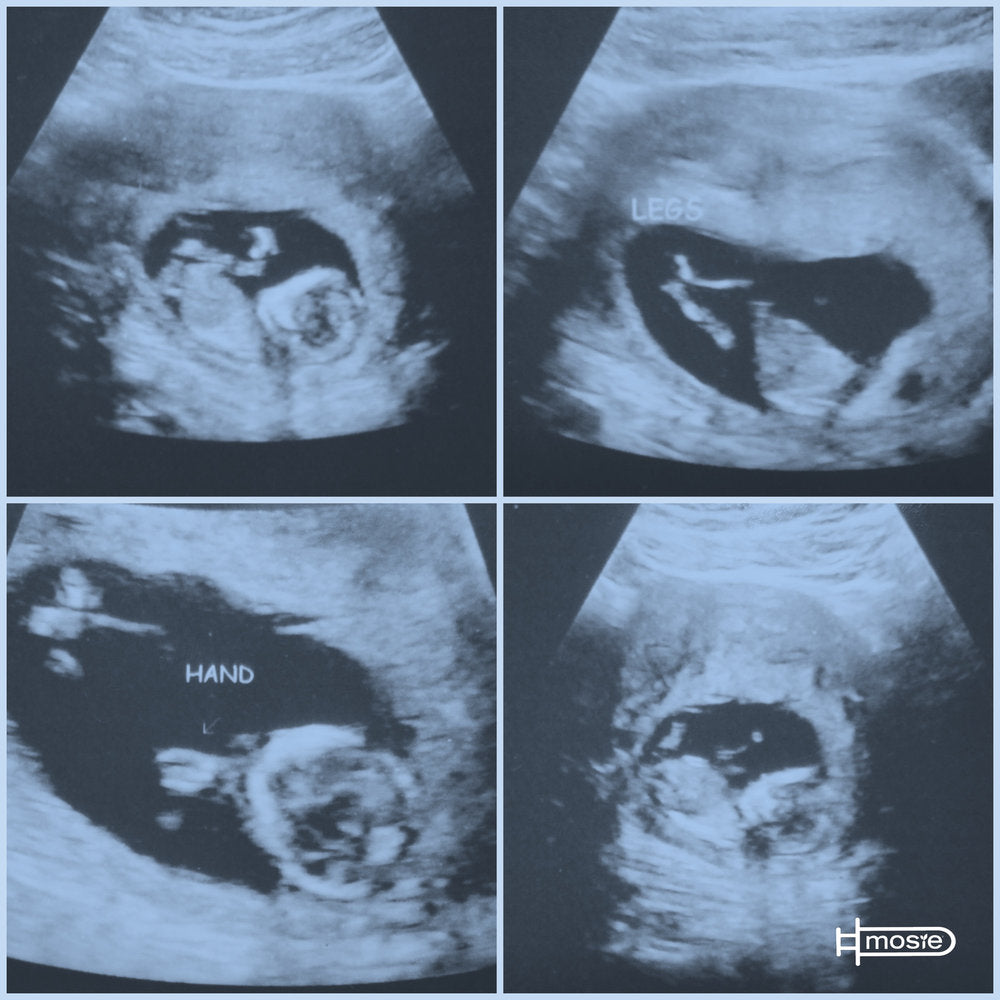

I went home that night and purchased a Mosie kit and we went for it. We had kinda watched BM cycle the month before so we had an idea of when to try: and hey we got two so we could try again if we were a little off. Following Maureen's instructions we waited, well i guess we didn't have to wait very long because two-ish weeks later (Oct 22) we got a +++++POSITIVE. BM is 24 weeks prego and we couldn't be happier!

A process we thought would be long and grueling turned out to be fast, easy, and comfortable not only for me, but for BM also. We both want to thank you Marc and Maureen from the bottom of our hearts for taking the complication out of this. For making it possible for people like us; that never even imaged it to be possible to have children of their own have the chance to conceive. This is a dream come true THANK YOU MOSIE BABY!!!!

"L" is 2 years old. Alicia and I can't thank you enough for the precious gift you've given us.

I see how much you guys have grown since we first read about Mosie Baby. It's been such a blessing I ran across your product. My daughter is the best thing to happen to both "A" and myself. And we have you to thank for it. You made the process easy and comfortable for both of us. I sing your praises constantly. I'm a forever cheerleader for Mosie Baby!! "A" and I would be honored to have baby girl featured. ^_^